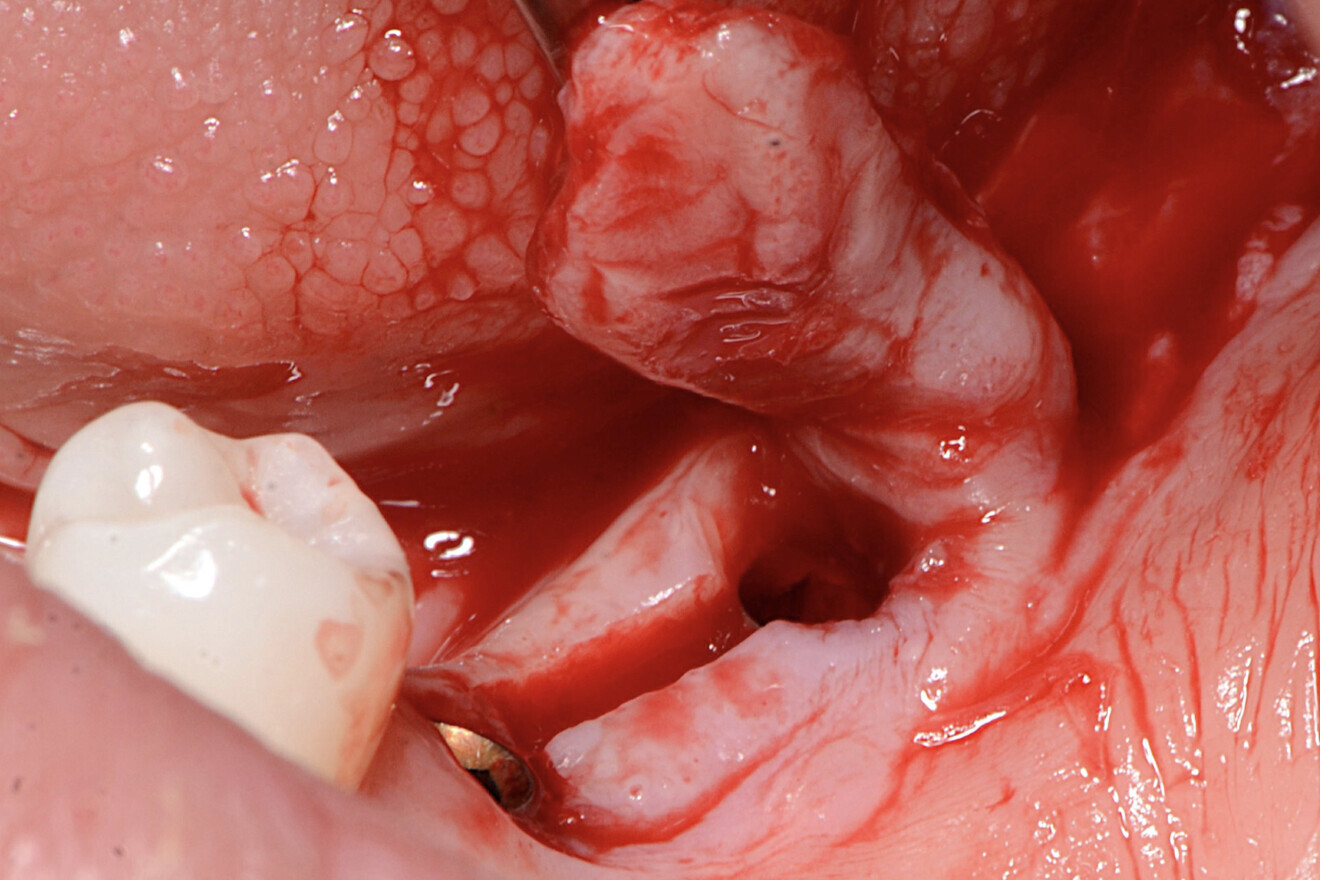

Fig. 1 : Situation préopératoire, montrant la zone concave entre les implants, favorisant la rétention de résidus alimentaires et la péri-implantite.

Le patient, 47 ans, présentait une résorption importante de la crête alvéolaire postérieure mandibulaire résultant de l’extraction des molaires (Fig. 1). Une récession gingivale péri-implantaire avec présence d’un tissu kératinisé minimal (moins de 1 mm) a été diagnostiquée au niveau de deux sites postérieurs. Le conditionnement des tissus mous péri-implantaires a été effectué quatre mois après la chirurgie implantaire.